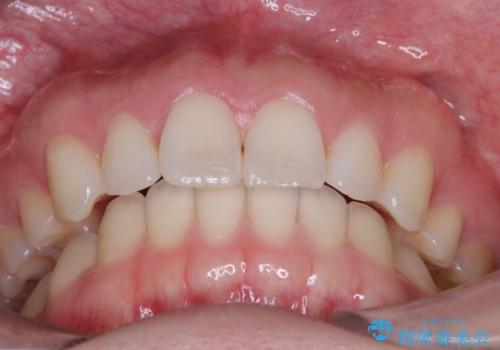

- 患者様は、上下顎の歯列不正と前歯部の突出感を主訴としてご来院されました。診断の結果、上顎左右第一小臼歯を抜歯することでスペースを確保し、歯列全体を整える方針としました。本来はワイヤー矯正が推奨されるケースですが、患者様のご希望により、透明なマウスピース型矯正装置「インビザライン」を使用した治療計画を立案しました。治療期間は約3年で、奥歯の噛み合わせを維持しながら、徐々に前歯の位置を整えました。

インビザラインは見た目の目立ちにくさと取り外しが可能な点がメリットですが、複雑なケースでは治療計画の精密さが求められます。本症例では奥歯の噛み合わせが崩れないよう注意を払いながら、マウスピースの交換タイミングを細かく設定しました。患者様には装着時間を守っていただくことが重要で、1日20時間以上の装着が必須です。また、抜歯部位のスペースを閉じる過程で、歯の動きが停滞しやすい時期もあるため、定期的なチェックを通じて治療が順調に進むよう管理しました。